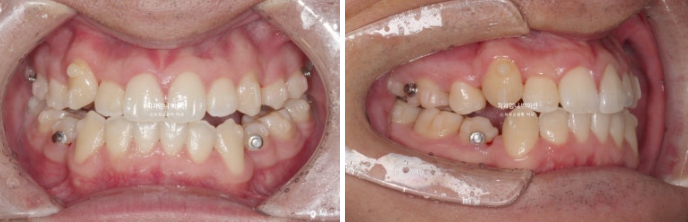

24년 1월 쓰러진 작은 어금니 치축을 개선하기 위해 재제작에 들어갔고 11월까지 첫번째 추가장치를 다 낀 모습입니다.

24.11

어금니 교합이 아직 미진하여 재제작을 한 번 더 했습니다.

어금니에 달린 동그란 것들은 고무주을 거는 고리 입니다.

배열은 좋습니다.

24년 12월부터 25년 4월까지 4개월간 두 번째 추가장치를 다 낀 후 치료를 종료하였습니다.